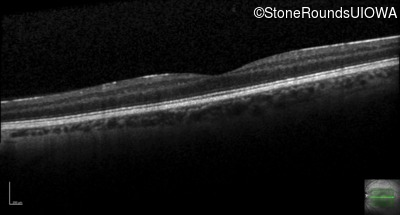

Age at visit: 31 years

OD OS

This 31 year old man has had poor acuity since early childhood.